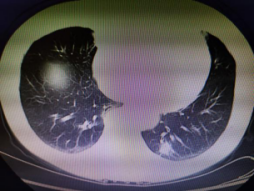

近日,一位高龄患者因体检发现左下肺占位,前往我院胸心外科就诊。在完善相关检查后,评估为肺恶性肿瘤可能性极大,必须及时切除。为最大限度减少手术产生的不良反应,艾成决定为患者实施创伤小、术后疼痛轻、恢复快的单孔胸腔镜下肺癌根治术。

术中先行肺占位楔形切除,冰冻活检证实为“腺癌”,遂进一步实施肺叶切除+系统淋巴结清扫术,两小时左右,手术顺利完成,术中出血不到50ml,手术切口仅3cm,患者恢复良好。

CT提示左下肺占位直径约20mm 手术中 单孔微创切口